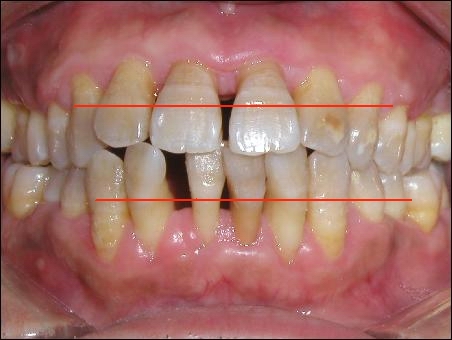

我在微信上發(fā)布了我拔牙的照片后,很多網友產生了疑問,牙齒看起來好好的,為什么要拔牙呢?

說實在的,這個療法還真的很有效,自那以后,我牙齦發(fā)炎的機率減少了很多。這次之所以下定決心拔牙,是因為我上面的兩個大門牙越長越難看,成了獠牙了,嚴重影響到我的形象,所以,不得不把掉。